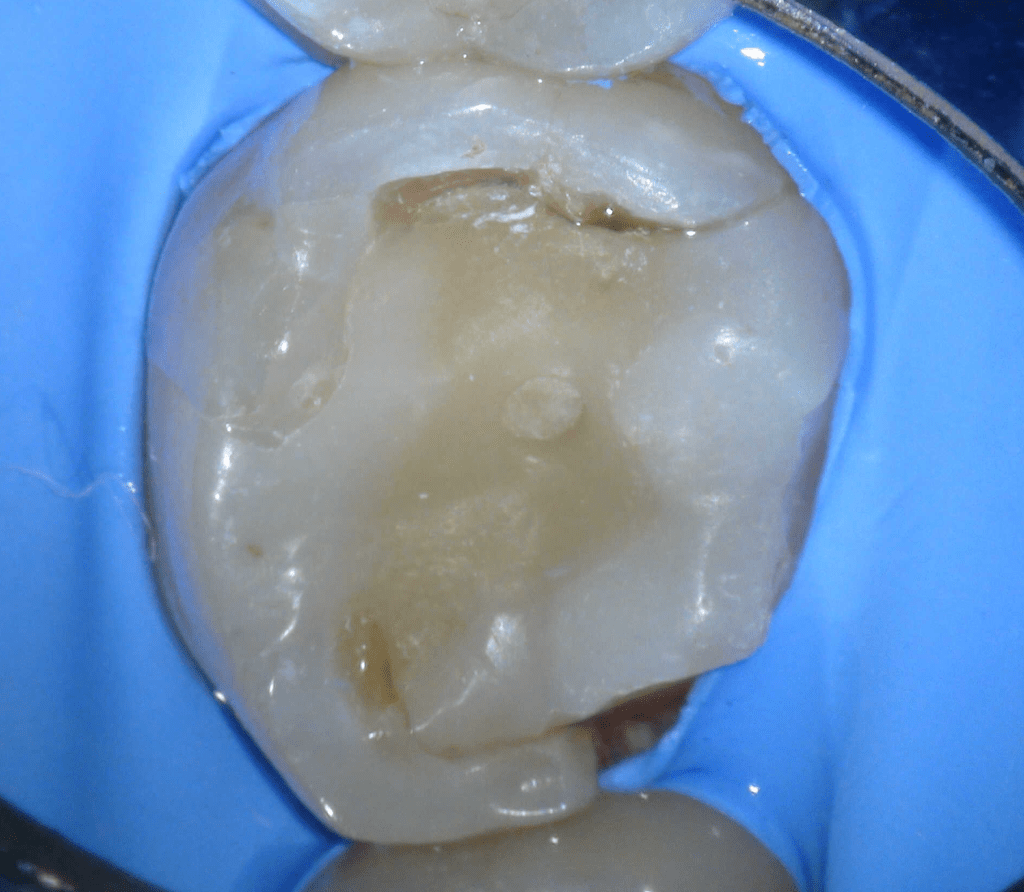

Pulpotomía biodentine + reco preendio